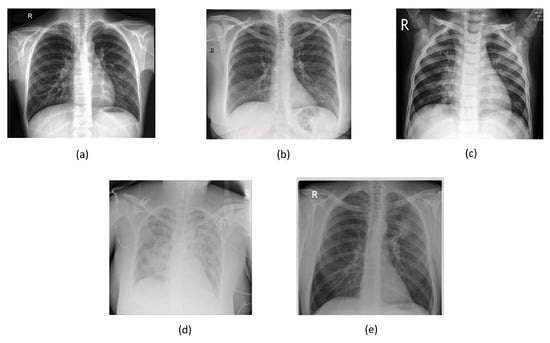

Figure 8 shows some examples of lung images, each corresponding to its respective pathology, with the classification percentage result for all classes. As can be observed, the model performs very well even on images it has never seen before, achieving a rate of accuracy ranging from 92 to 99%.

Figure 8. Lung disease classification for (a) “normal”, (b) “covid”, (c) “pneumonia”, (d) “lung_opacity”, and (e) “tuberculosis” classes using testing set.